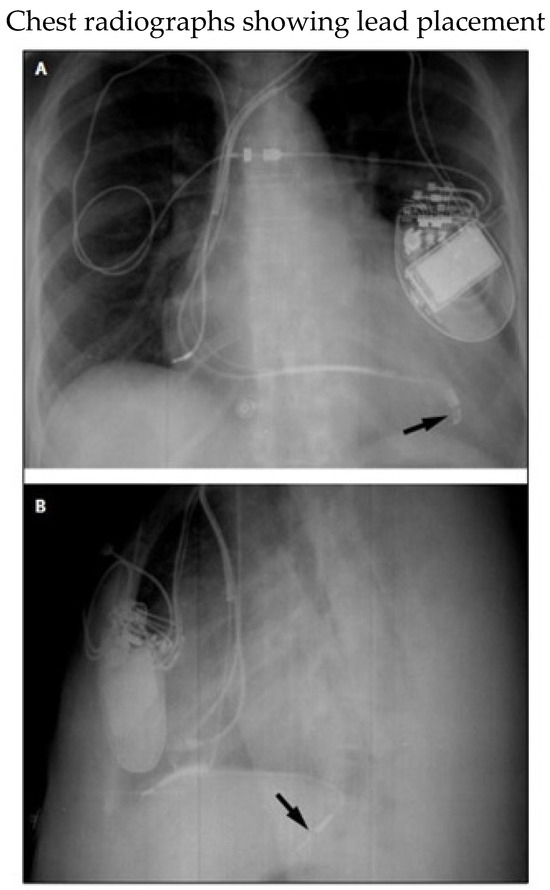

Figure 5. (A) Posteroanterior and (B) lateral radiographs showing tip of left ventricular lead (arrows) in a tributary of the middle cardiac vein. Despite proximity to the left hemidiaphragm, phrenic near stimulation did not take place. The right ventricular lead points anteriorly toward the rib cage. Reproduced from reference [78] with permission.

Cardiac physiological pacing (CPP) refers to any form of cardiac pacing intended to restore or preserve synchrony of ventricular contraction. Biventricular (BiV) pacing is the most common method used to achieve resynchronization. Left ventricular leads are usually implanted epicardially via the coronary sinus (CS) into the cardiac veins (Figure 5), ideally targeting areas of late activation (most often the lateral or posterolateral wall) [77,78]. When CRT cannot be obtained with a CS LV lead due to anatomical or functional considerations, options include surgical placement of an epicardial lead, His-bundle pacing and left bundle branch pacing [77]. His-bundle pacing has been limited by relatively high pacing thresholds and lead instability. Left bundle branch pacing has been increasingly used because it overcomes those issues and is more likely to result in the narrowing of the QRS complex when conduction disease is more distal [79].